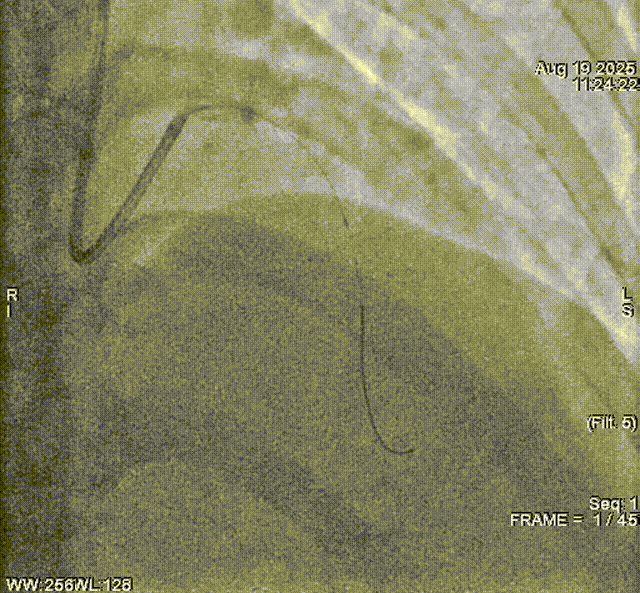

冠脉造影

冠脉造影示前降支近段95%狭窄。经攀枝花市中心医院心血管团队评估,考虑行IVUS指导下PTCA及生物可吸收支架植入术。

术前造影示前降支狭窄